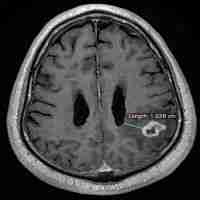

| Abstract | Despite current strategies combining surgery, radiation, and chemotherapy, glioblastoma (GBM) is the most common and aggressive malignant primary brain tumor in adults. Tumor location plays a key role in the prognosis of patients, with GBM tumors located in close proximity to the lateral ventricles (LVs) resulting in worse survival expectancy and higher incidence of distal recurrence. Though the reason for worse prognosis in these patients remains unknown, it may be due to proximity to the subventricular zone (SVZ) neurogenic niche contained within the lateral wall of the LVs. We present a novel rodent model to analyze the bidirectional signaling between GBM tumors and cells contained within the SVZ. Patient-derived GBM cells expressing GFP and luciferase were engrafted at locations proximal, intermediate, and distal to the LVs in immunosuppressed mice. Mice were either sacrificed after 4 weeks for immunohistochemical analysis of the tumor and SVZ or maintained for survival analysis. Analysis of the GFP+ tumor bulk revealed that GBM tumors proximal to the LV show increased levels of proliferation and tumor growth than LV-distal counterparts and is accompanied by decreased median survival. Conversely, numbers of innate proliferative cells, neural stem cells (NSCs), migratory cells and progenitors contained within the SVZ are decreased as a result of GBM proximity to the LV. These results indicate that our rodent model is able to accurately recapitulate several of the clinical aspects of LV-associated GBM, including increased tumor growth and decreased median survival. Additionally, we have found the neurogenic and cell division process of the SVZ in these adult mice is negatively influenced according to the presence and proximity of the tumor mass. This model will be invaluable for further investigation into the bidirectional signaling between GBM and the neurogenic cell populations of the SVZ. |